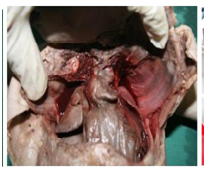

Atrioventricular circumference was measured (Figure 3) using a paquimeter. The anterior and posterior cusps of mitral valve were identified (Figure 4). The bicuspid valve along with annulus, chordae tendinae and papillary muscles were removed by dividing its ring at the lateral commissure and by half splitting the medial papillary muscle mass as described in literature.3

Figure 4 Showing anterior and posterior cusps, papillary muscles and chordae tendinea.